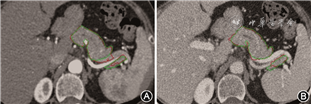

2. 客观评价系统:客观评价方法采用DSC。两名医师先分别评价动脉期,2周后评价静脉期的分割效果,当两者得分不一致时,引入高年资医师评分(图1)。